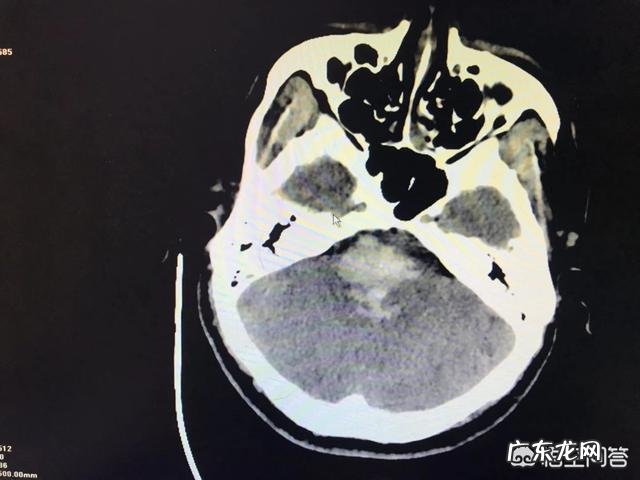

为什么有些高血压患者天天吃降压药,但还是会脑出血?【最后一支多巴胺】急诊执业医师,遇见许多人,碰见许多事 。为什么有些高血压患者天天吃药,还是会出现脑出血?

文章插图

这是一个困扰很多人的问题,也是一个让很多高血压患者不安的疑虑 。

但是,这位问题看似很有理,其实是有很多“内幕”的 。